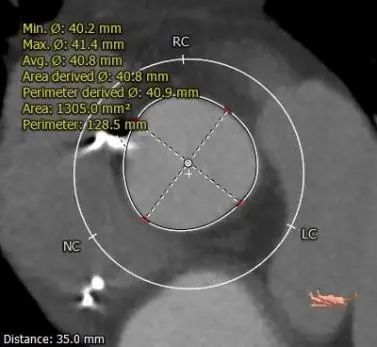

主动脉根部测量

瓣上测量

1.Type 0 型二叶瓣,瓣叶增厚,双侧瓣叶边缘连续条状钙化,瓣膜锚定难度适中,瓣膜植入受两侧钙化挤压存在移位风险及瓣周漏风险。

2.冠脉开口高度可,未见冗长瓣叶,结合瓦氏窦、STJ内径综合预估,冠脉风险适中。